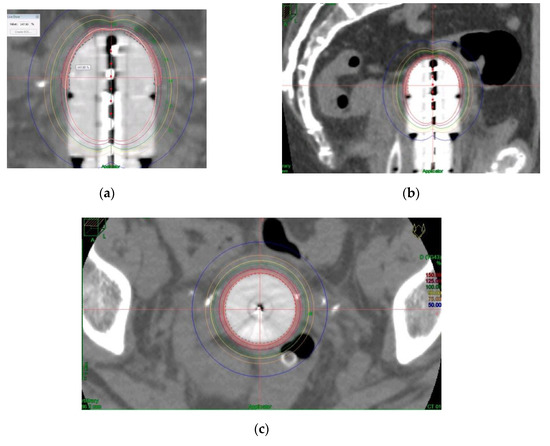

The dose was prescribed at a depth of 5 mm from the applicator surface, and point dose optimization based on distance was used. The active treatment length was 2.5 cm. In the present study, 90% of the isodose surface included the CTV. The voxels corresponding to the vaginal D2cc are always located in a small volume at the top of the vaginal-cuff and any reduction in the dose at this level will consequently reduce the dose at the prescription point. This 2cc volume is described and presented in Figure 3.

Figure 3.

Example of dosimetric study showing the most exposed 2 cm3 of vagina to the dose in coronal (a), sagittal (b) and axial (c) planes and (d) dose volume histogram.

Distension of the rectum and air gaps have no impact on the D2cc of vagina considering that the 90% isodose always includes the CTV. The minimum dose of 90% received by 90% of the hottest CTV volume (D90) and the percentage of CTV coverage were calculated as well as the dose to the most exposed 2 cm3 of the rectum, bladder, and vagina. An EQD2(α/β = 3Gy) constraint of 65Gy for rectum and 80Gy for bladder were applied but were never necessary. Dose distribution was not modified to exclude the organs at risk from the dose prescription area. Figure 2 shows the dosimetric study with the area of the vagina most exposed to the dose. After dosimetric evaluation patients underwent treatment with an HDR microSelectron v2 Iridium 192 source and an afterloading source projector (Nucletron® microSelectron V3 digital ELEKTA, Holland, The Netherlands).